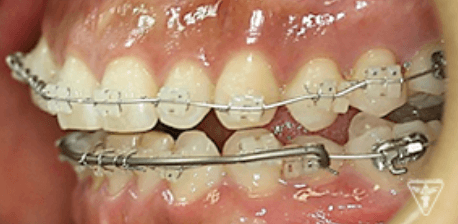

治療過程③